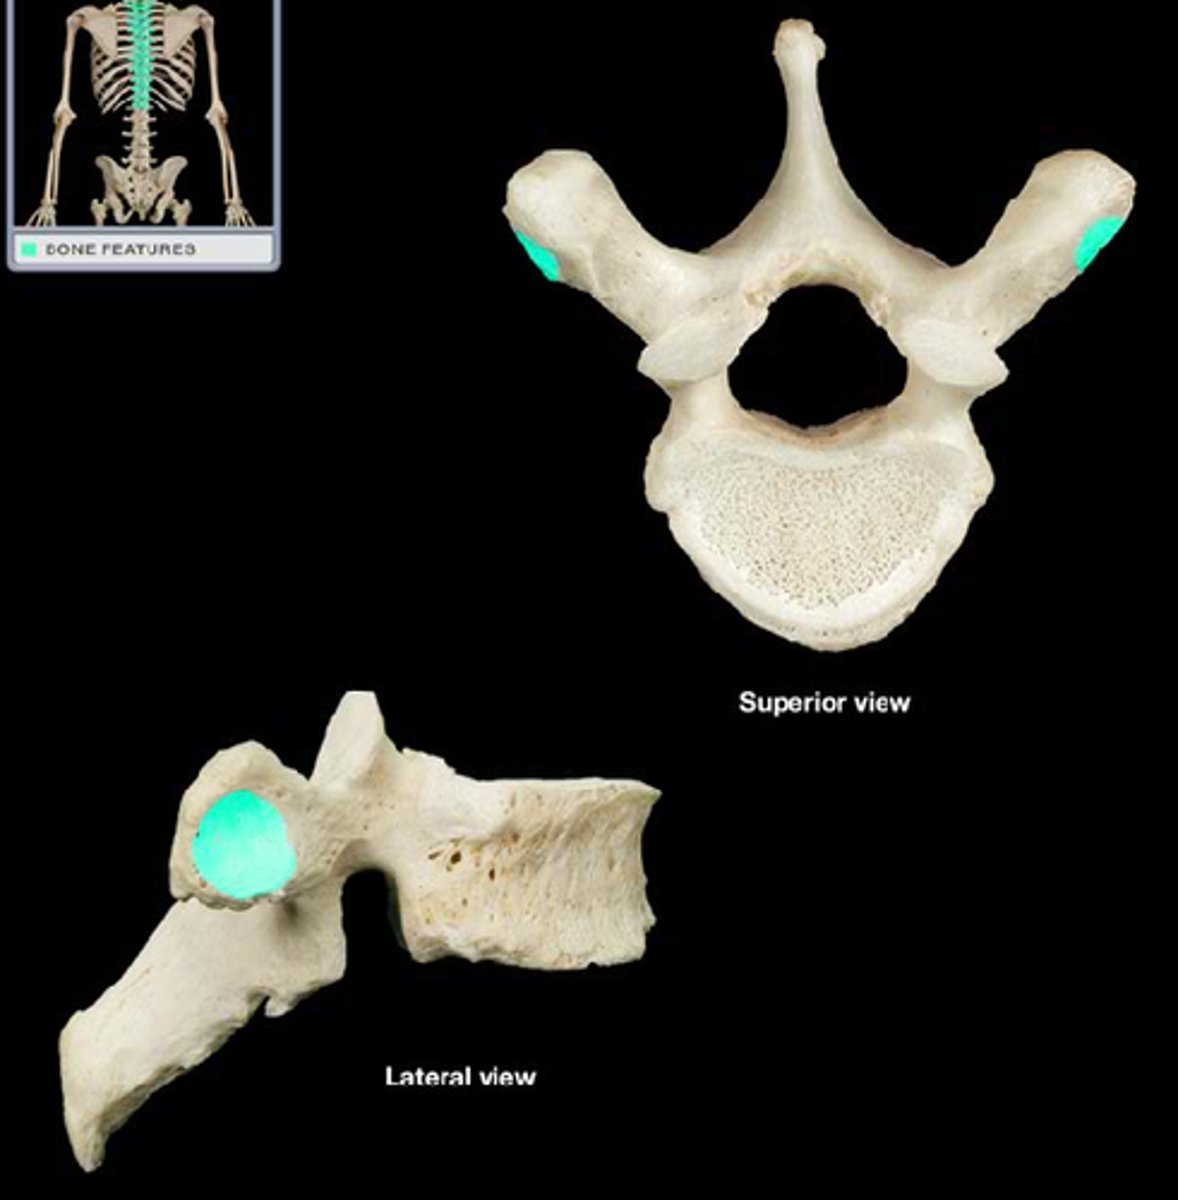

transverse process

transverse formen (cervical)

the transverse formean (where vertebral artery passes thru)

what structure is the distingushing feature of the cervical vertebra